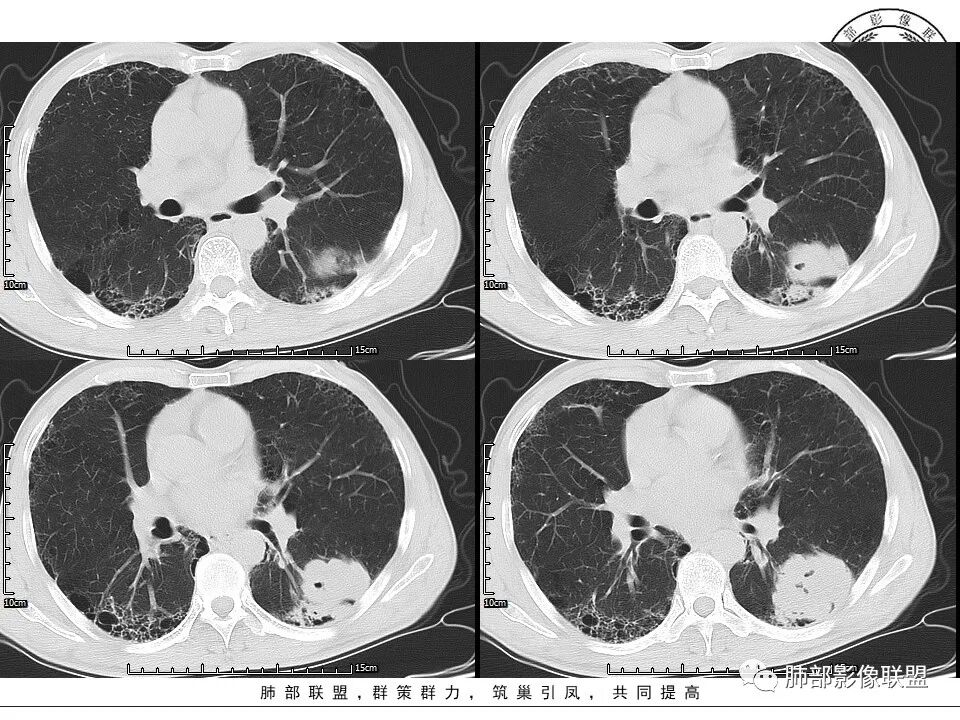

1、老年男性,肺气肿背景,咳嗽胸闷一个月,血象不高,C反应蛋白无明显升高,无发热。

2、左肺下叶近胸膜下较大肿块,土豆样外形,边缘清楚,膨隆分叶,未见明显渗出;病灶内部多坏死及空洞,似鬼脸征,坏死边界不清;增强扫描轻度不均匀环形强化;近端支气管似有阻塞截断。肺门纵隔未见肿大淋巴结。

3、综上所述,考虑恶性,鳞癌可能。

患者中老年男性,咳嗽、胸闷1月余。查肝肾功能、血糖、血脂、心肌酶异常不明显;血常规提示血象不高,轻度贫血;血沉、C反应蛋白、降钙素原无明显升高。胸部CT:肺气肿背景,左肺下叶胸膜下不规则肿块,边缘光滑,边界清楚,见浅分叶,其内见多发分隔空洞及坏死,似鬼脸征,支气管显示欠清,增强不均匀强化。右肺下叶胸膜下间质纤维化改变。综合肿块考虑恶性病变,鳞癌或肉瘤样癌可能大,鉴别隐球菌。